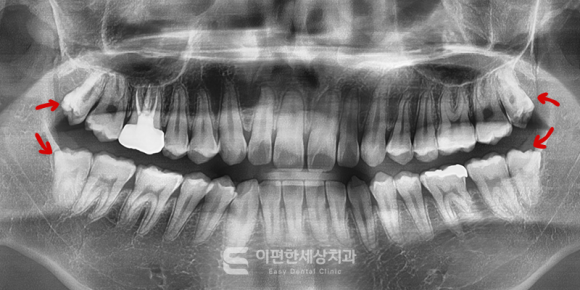

촬영일자 : 2024. 05. 27

※이해를 돕기 위한 참고용 이미지입니다.

치과에서는 보통 파노라마 엑스레이 촬영이나

3D CT 촬영을 통해 신경과의 위치 관계

매복 정도, 맹출 각도 및 방향 등을 꼼꼼하게 확인한 후에

발치 계획을 세우게 됩니다.